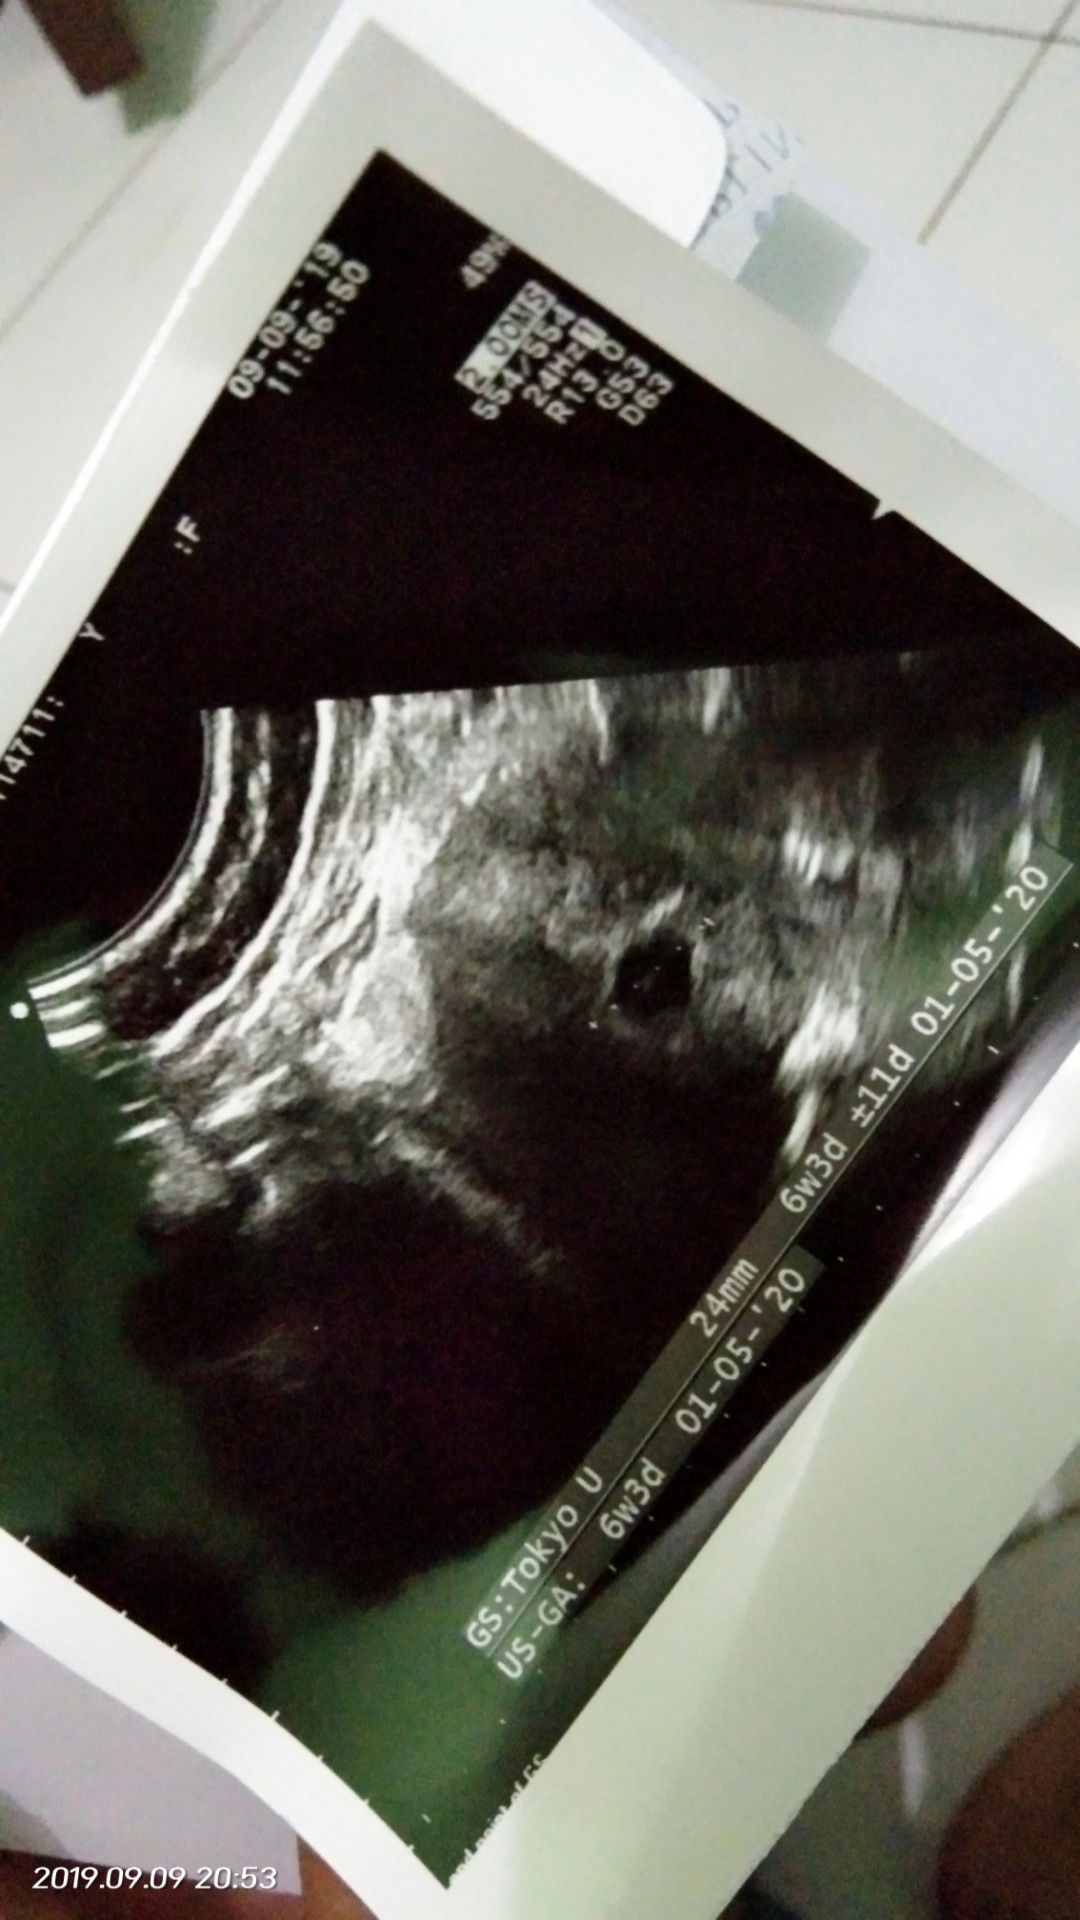

Hai para moms yg berbahagia mau tanya saya dr usia kehamilan 1 mnggu smpai skrng 7 mnggu knpa tidak mengalami mual dn pusing ya .. Tp saya sudah usg janin nya sudh tumbuh sperti ini ... Apakah ini normal ?? Terimakasih